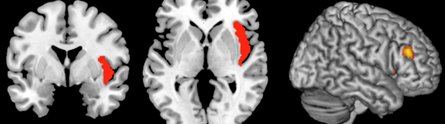

Brain scan showing the insula area of the brain

In a study published today in the leading journal Neuron, they have demonstrated that the severity of symptoms such as delusions and hallucinations which are typical in patients with the psychiatric disorder is caused by a disconnection between two important regions in the brain — the insula and the lateral frontal cortex.

The four-year study, led by Professor Peter Liddle and Dr Lena Palaniyappan in the University’s Division of Psychiatry and based in the Institute of Mental Health, centred on the insula region, a segregated ‘island’ buried deep within the brain, which is responsible for seamless switching between inner and outer world.

The insular and frontal cortex form a sensitive ‘salience’ loop within the brain — the insular should stimulate the frontal cortex while in turn the frontal cortex should inhibit the insula — but in patients with schizophrenia this system was found to be seriously compromised.